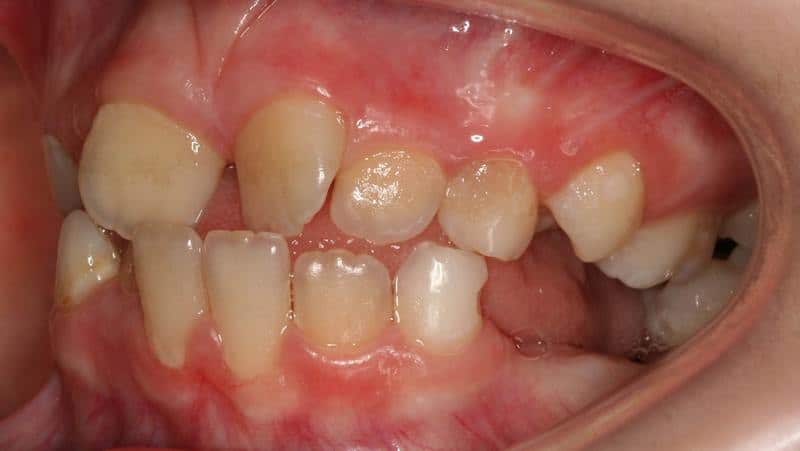

Откуда берется тортоаномалия: основные причины отклонения

Что может стать предпосылкой для поворота одного или нескольких зубов? Можно выделить 5 основных предпосылок:

- Отсутствие физиологически необходимого для зуба пространства, связанное с макродентией или специфически узкой челюстью. Данная причина проста и понятна: зуб просто не может поместиться в отведенное ему место, не развернувшись. Характерной особенностью такой аномалии является угол поворота в 45° – именно так зуб занимает наименьшее пространство в уже сформировавшемся челюстном ряду, также стоит упомянуть и сложность исправления дефекта : в некоторых случаях это просто невозможно из-за особенностей челюсти.

- Подверженность зуба постоянному давлению. Такая ситуация может быть вызвана сверхкомплектными или активно, но не совсем физиологически правильно (например с задержкой) прорезывающимися соседними зубами. Под действием постоянного бокового или нижнего давления (иногда с нескольких сторон) зуб несколько проворачивается в гнезде – и вот она типичная тортоаномалия.